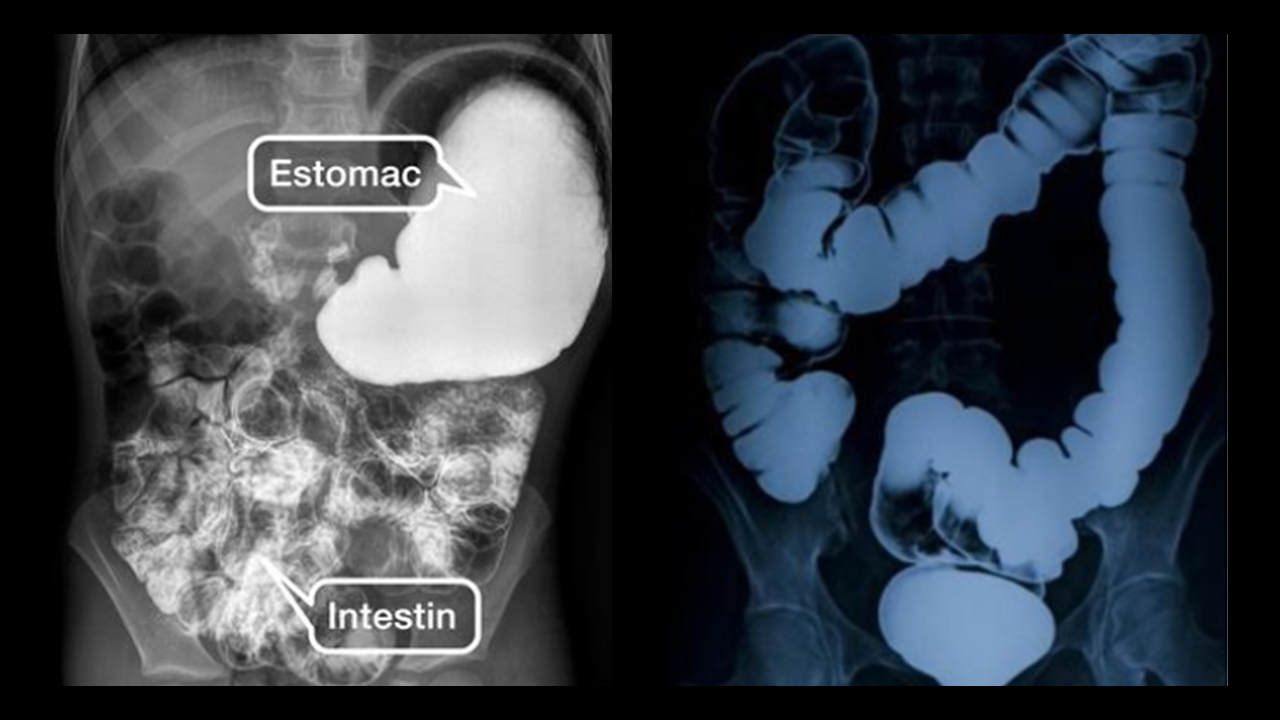

Complément : Le système digestif... vu de l’intérieur !

Le système digestif est composé du tube digestif dans lequel passent les aliments, et de glandes annexes : salivaires, foie, pancréas.

Le schéma ❤️ BILAN ci-dessus est à connaitre !